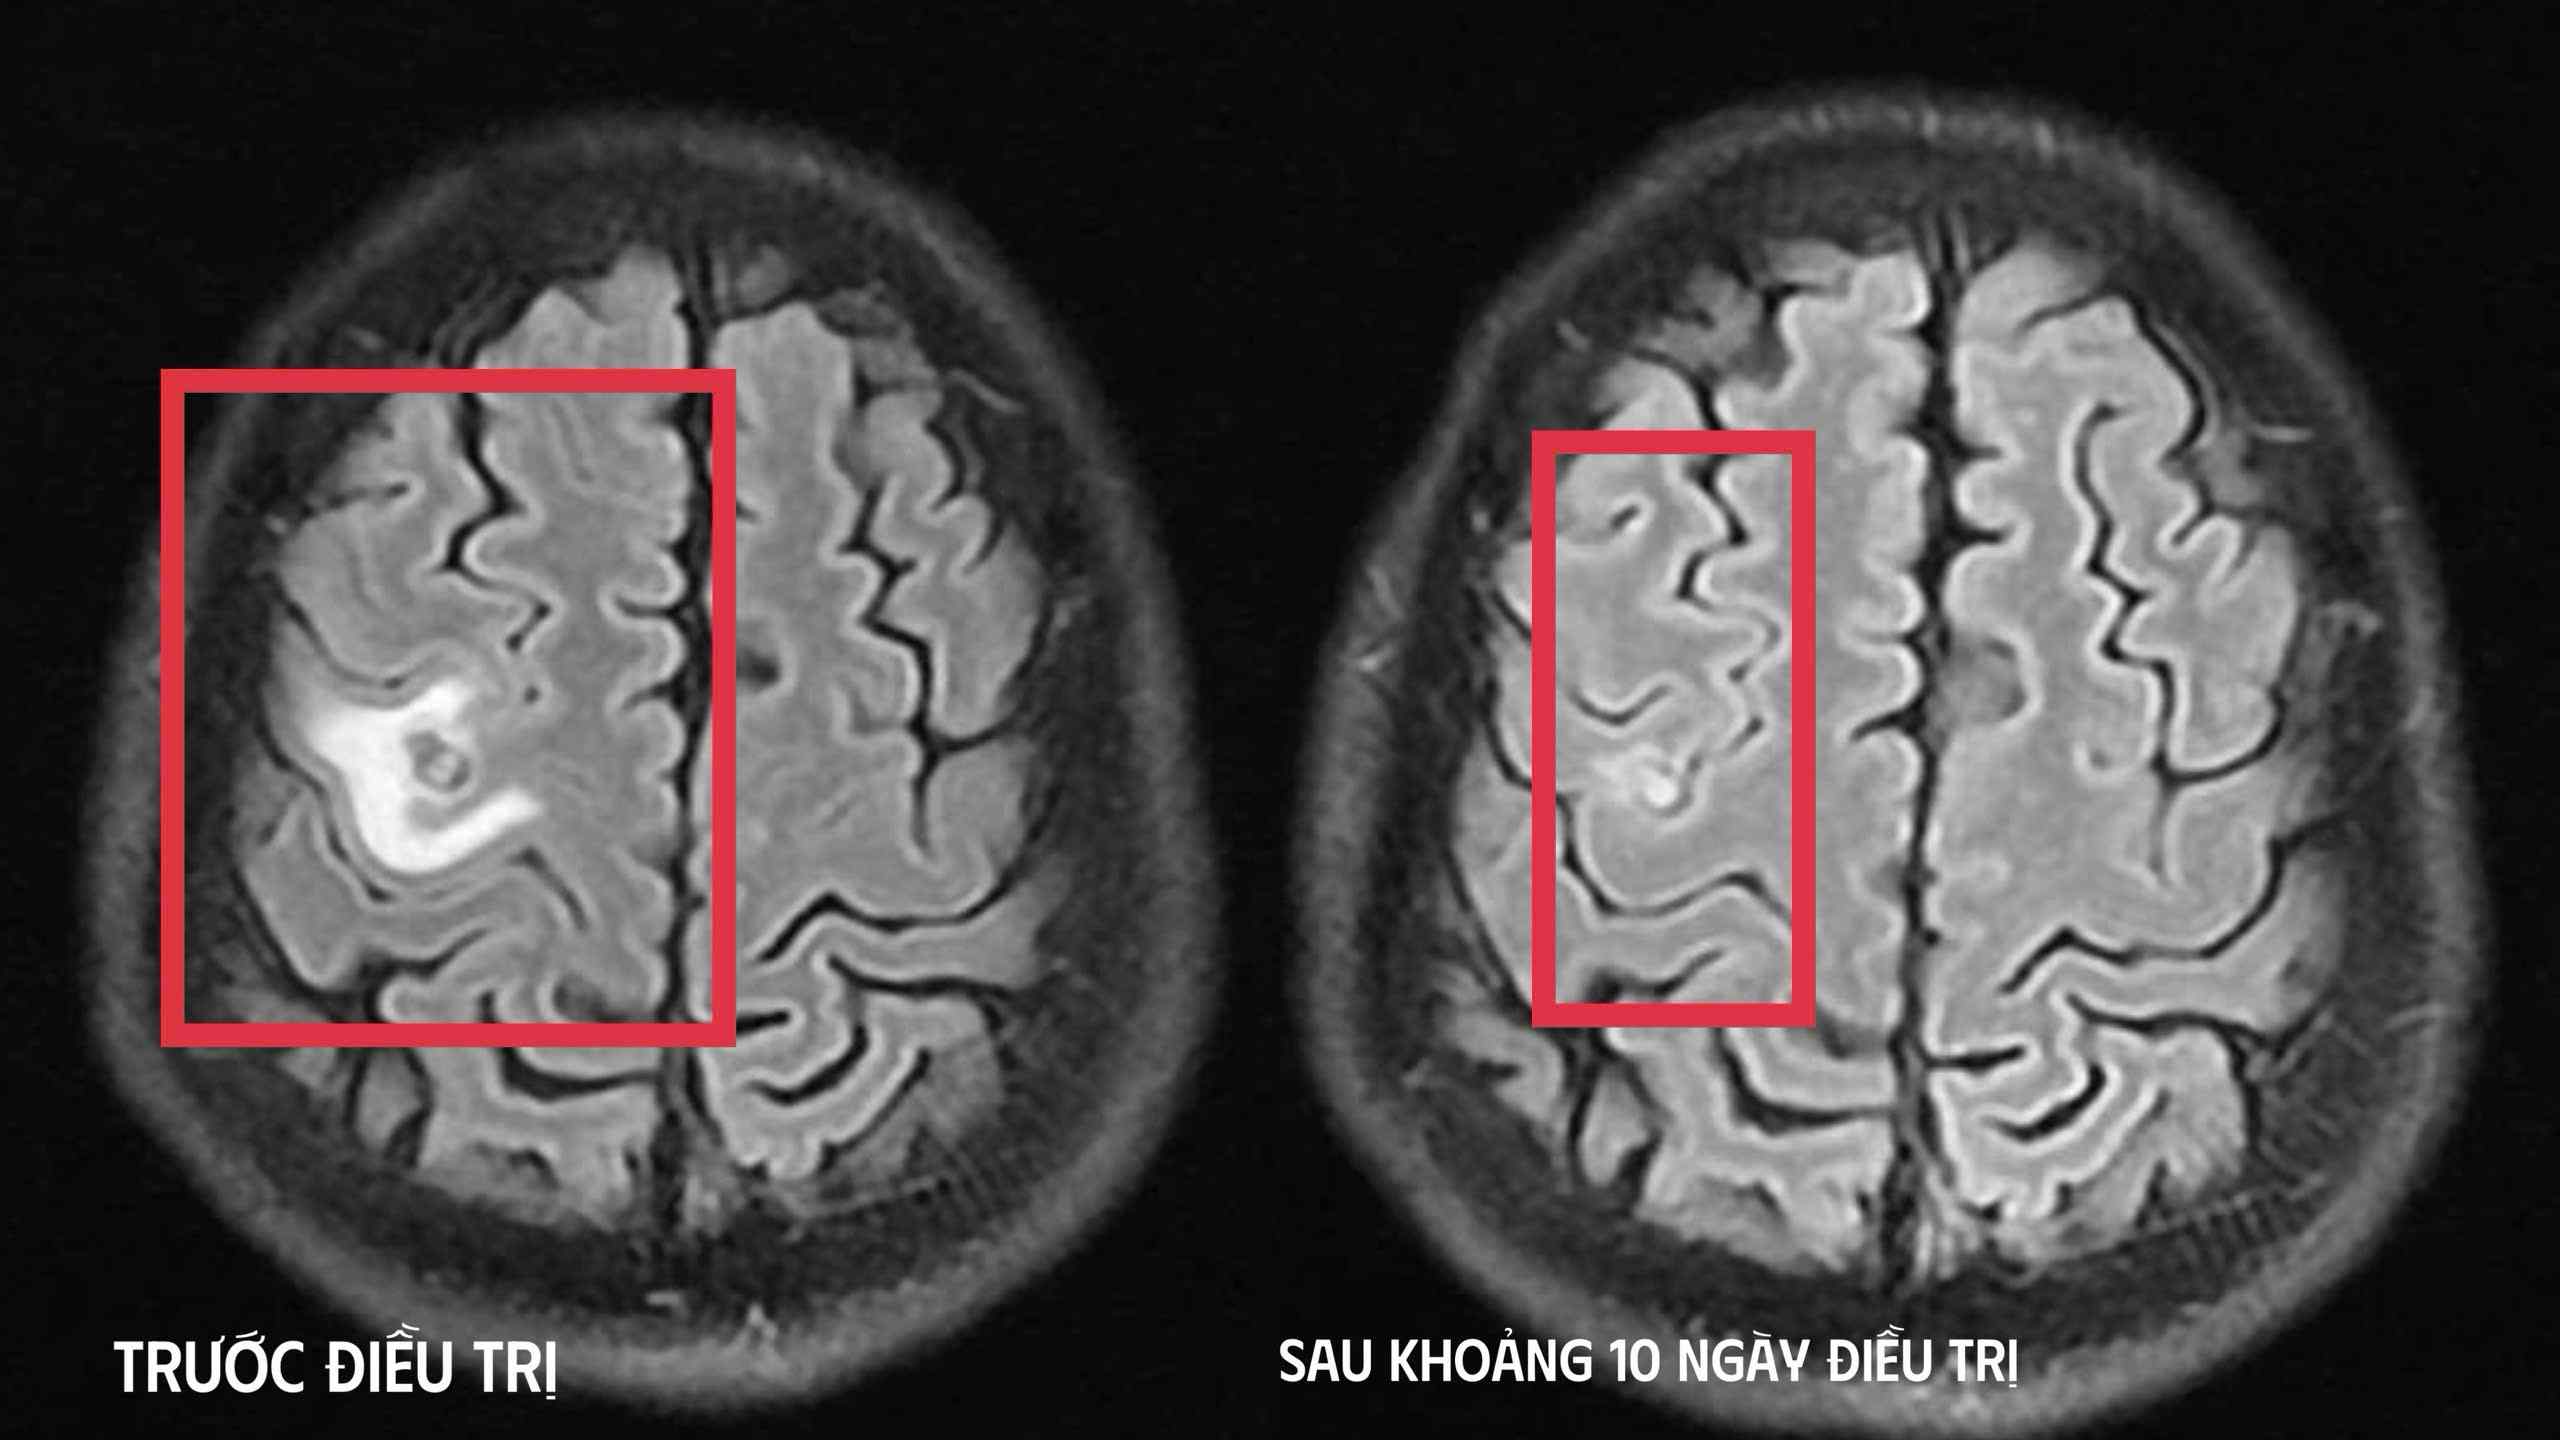

Sau khi các bác sĩ thăm khám và chụp cộng hưởng từ sọ não phát hiện một nang nhỏ ở thùy trán trái, kích thước khoảng 11 x 7 mm, kèm phù não nhẹ. Hình ảnh gợi ý tổn thương do ký sinh trùng hơn là u não nguyên phát. Xét nghiệm huyết thanh học kháng thể kháng sán dây chó dương tính, xác định chẩn đoán tổn thương não do ký sinh trùng.

Bệnh nhân được điều trị theo phác đồ, kiểm soát triệu chứng và theo dõi sát diễn biến thần kinh. Sau 10 ngày, tình trạng cải thiện rõ rệt, bệnh nhân hết tê tay, không co giật, đau đầu hay chóng mặt biến mất, toàn trạng ổn định. Bệnh nhân xuất viện và tiếp tục điều trị ngoại trú đủ liệu trình 4 tuần.

Khi tái khám gần một tháng sau, chụp cộng hưởng từ cho thấy nang não thu nhỏ rõ, phù não giảm, không còn dấu hiệu tiến triển, đáp ứng điều trị tốt.